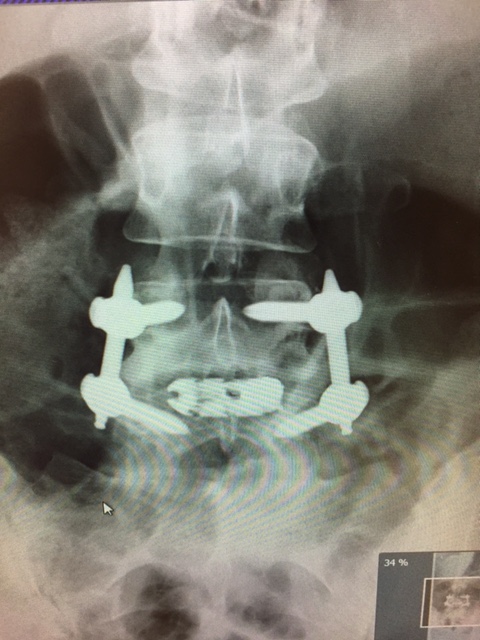

the metal work Published April 18, 2017 at 480 × 640 in My Story: Lumbar Fusion Surgery Week 1 ← Previous Next →